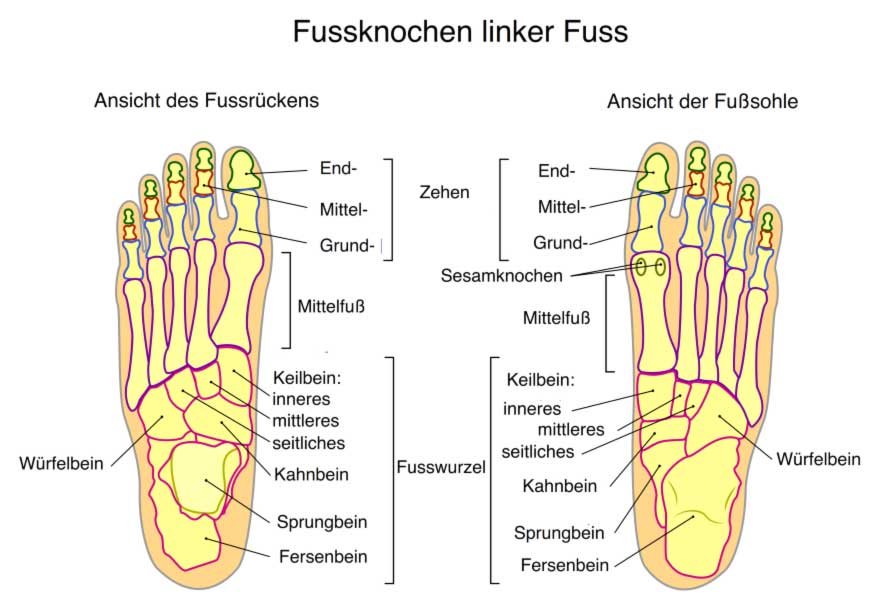

Fußanatomie: Lerne Deine Füße Kennen! – GetSteps

Fuß Füße Sprunggelenk Zehen Arztpraxis Lüneburg Dr. Med. Thomas Hartmann